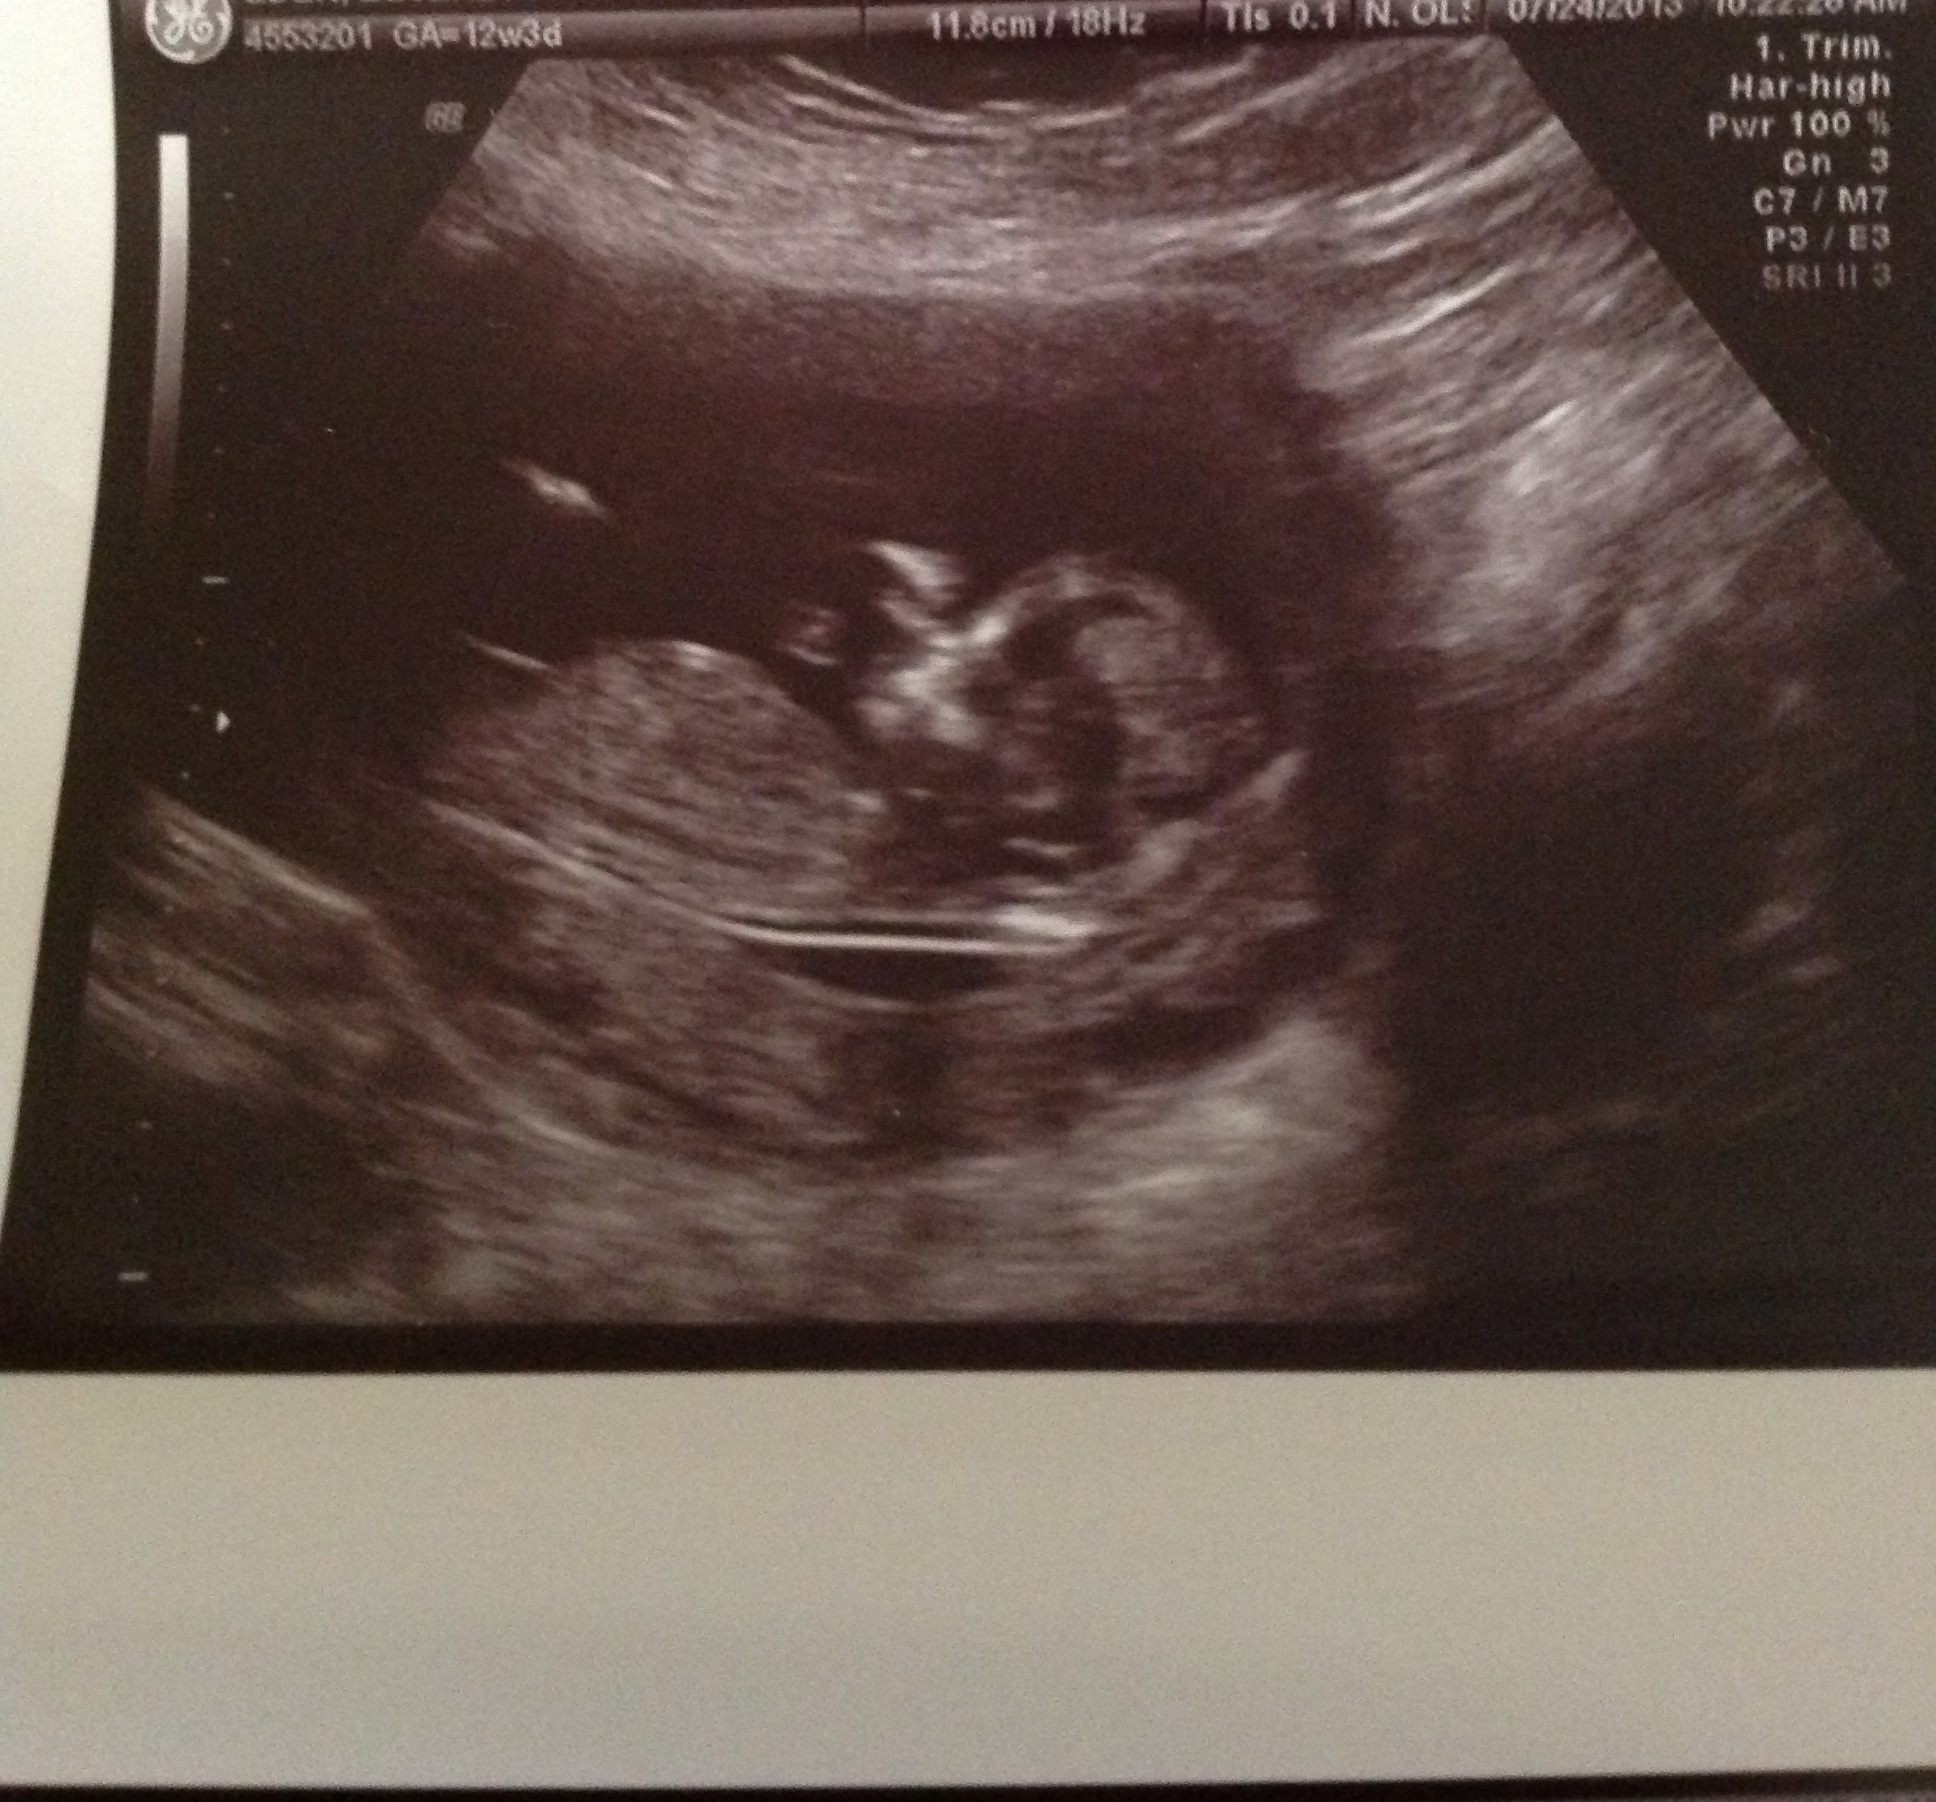

I hope this works...not the best pic, but it's all we got!! 12 weeks & 4 days along!!

Not sure if all the details there but if it is I guess girl:) Massive congratulations to your friend WeadinWom;)

Unfortunately all the nub isn't visible....but if I had to guess I would lean towards girl...

leaning pink

I think the nub may be a little cut off at the end but I think it's very flat and if your tech said that, wow, just wow.

yours is such a girly nub, and by 14 weeks I would expect far more rise and definition for a boy. My money is on a girl for you.

12 weeks 4 days...but measuring 12 weeks 5 days.